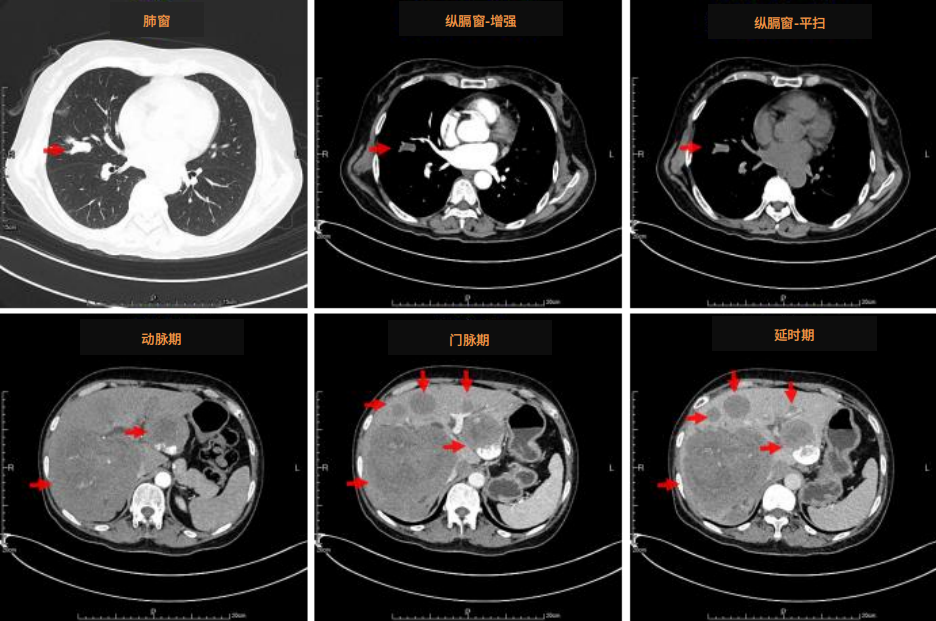

3)18FDG-PET/CT(2023/1/7)

右肺中叶外侧段见分叶结节影,直径约1.4cm,SUVmax约2.2,病灶邻近支气管内见条状密度增高影,SUVmax值约3.3;肝内多发肿块,代谢增高,较大者位于肝右叶,最大横截面约9.4cm×10.0cm,其内伴多发坏死,边缘多发结节状代谢增高,SUVmax约10.5;L4、5椎体代谢增高影,SUVmax约4.4,考虑为骨转移可能,余脊柱代谢不均,转移不除外(图1)。

图1 患者18F-FDG PET/CT图像